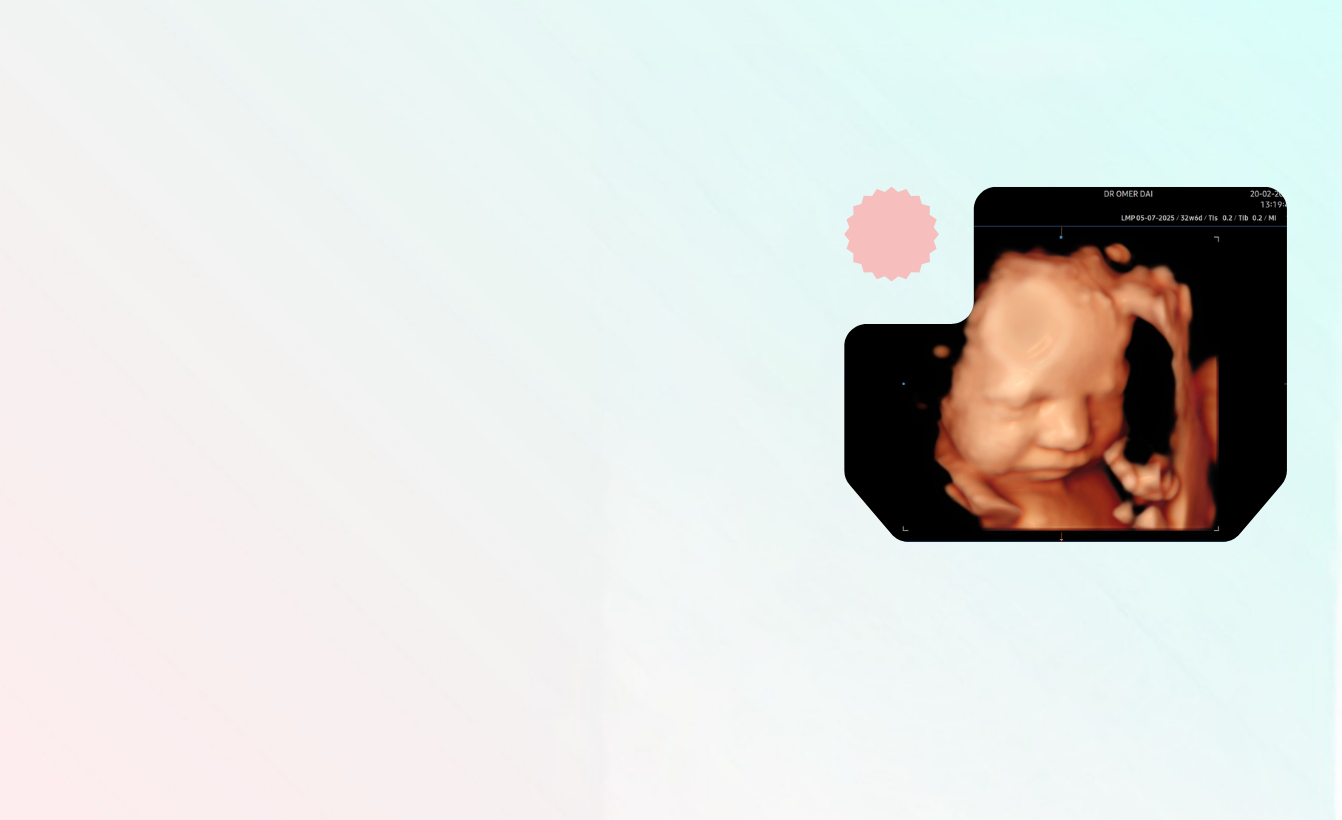

Pregna Mucizler Sergisi

Bizim her gün gördümüz mucizeleri sizlerle paylaşmak istedik